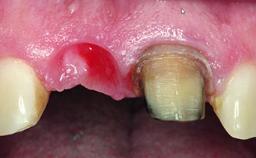

A healthy 37-year-old female patient was referred for a consultation on the replacement of missing tooth 21 with an implant-supported restoration. She stated that several years previously the tooth had been traumatically avulsed following a motor vehicle accident. The tooth was replaced with a three-unit fixed partial denture (FPD) immediately afterwards. Over time, she became disillusioned with the FPD and looked for a different option, including orthodontic therapy. She presented still in her orthodontic appliances, with the pontic sectioned free from the FPD but attached to the archwire. Her orthodontist felt that orthodontic treatment had been successfully completed, but nevertheless referred her before removing the appliances in case adjustments were necessary.

Soft Tissue Anatomy Intact Defective

Bone Volume Horizontally and vertically sufficient Horizontally deficient Deficient vertically or deficient vertically AND horizontally

Bone Volume Deficient horizontally, allowing simultaneous augumentation